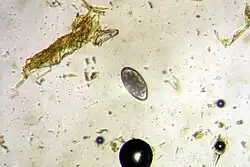

| Haemonchus contortus egg | |

The ova is yellowish in color. The egg is about 70–85 μm long by 44 μm wide, and the early stages of cleavage contain between 16 and 32 cells. The adult female is 18–30 millimetres (3⁄4–1+1⁄8 in) long and is easily recognized by its trademark "barber pole" coloration. The red and white appearance is because H. contortus is a blood feeder, and the white ovaries can be seen coiled around the blood-filled intestine. The male adult worm is much smaller at 10–20 millimetres (3⁄8–13⁄16 in) long, and displays the distinct feature of a well-developed copulatory bursa, containing an asymmetrical dorsal lobe and a Y-shaped dorsal ray.